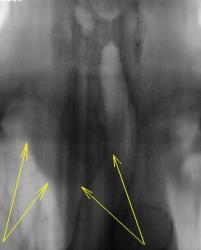

На мой взгляд, слева на верхушке в медиальных отделах верхушеного сегмента (1+2) некоторая динамика есть, да и "кругляк" справа на верхушке (средостении) на 11 срезе, субъективно дифференцируется лучше.